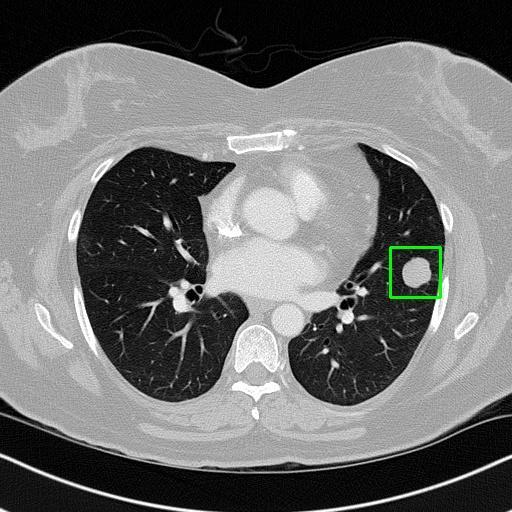

We developed an AI-based system using deep learning models for analyzing lung CT scans to detect and classify pulmonary nodules. We chose the YOLOv11 architecture for its enhanced object detection capability and adapted it specifically for medical imaging, incorporating pixel-level precision and severity classification.

Classification into three severity levels with colored bounding boxes.

Successfully built and deployed an AI model (YOLOv11) capable of detecting lung nodules in CT scans with high accuracy and real-time performance.

Designed a severity classification system that categorizes nodules into null, moderate, and severe using colored bounding boxes, assisting in rapid clinical decision-making.